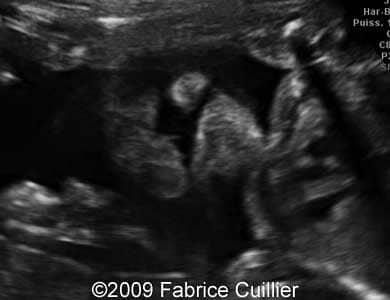

The following images show a case of an unilateral cleft lip diagnosed at 25 weeks old fetus of a 22-year-old mother with non-contributive history. No other anomaly was found. Karyotyping revealed normal karyotype (46,XX) and the course of the pregnancy was uneventful. The neonate was delivered at 38 weeks and its surgery is scheduled at six months.

Images 1, 2, 3: 2D images showing unilateral cleft lip.